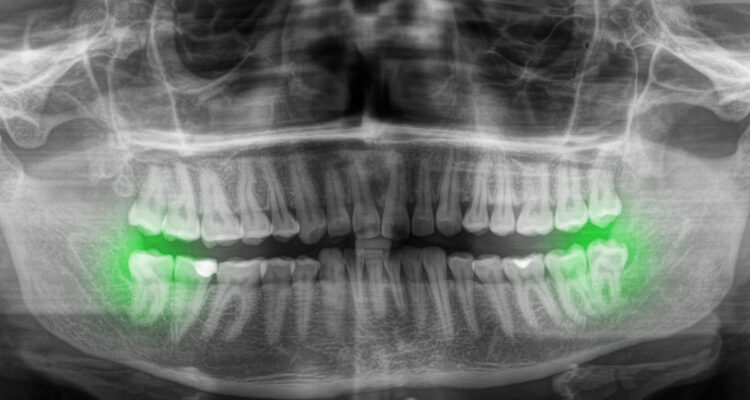

Нужно ли удалять зуб мудрости, если он не болит?

При нормальном прорезывании, развитии и росте зуба мудрости его удаление не производится. Если эти процессы осложняются перикоронитом, значительным кариесом, воспалительными заболеваниями полости рта, дистопией зубов или травмами, то врачи-стоматологи рекомендуют удаление.

Не нужно удалять

Нужно удалять